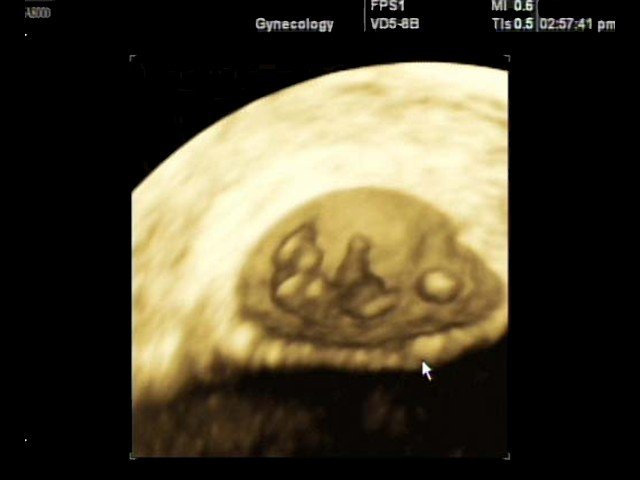

SonoAce-8000 Live - многофункциональный ультразвуковой сканер, 3D Live модификация аппарата SonoAce-8000 компании Medison с цветным, энергетическим, тканевым, импульсным и непрерывноволновым допплером, трехмерным УЗИ в реальном времени (4D объемными датчики).

- Система Live 3D - возможность проведения трехмерного УЗИ в реальном времени (4D):

- 3D датчики;

- получение любого среза в каждой из 3-х проекций;

- получение трехмерных изображений в режиме серой шкалы, а также цветного и энергетического допплера;

- кинопетля в 3D режиме;

- фото-режим;

- измерения в трехмерном режиме;

- функция автоматического вычисления объема структур сложной формы. - SonoAtlas - программа обучения проведению ультразвуковой диагностики (электронный учебник с примерами эхограмм и описанием методики их получения).

Объемный датчик 3D 3-5EK/40/69

Трехмерные абдоминальные исследования, акушерство и гинекология.

Биопсийный набор: есть.

Объемный датчик 3D 4-8ET/40/84

Трехмерные абдоминальные исследования, акушерство (трехмерное УЗИ плода) и гинекология.